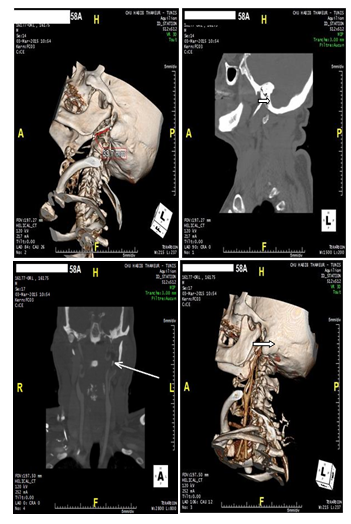

Patient 58 year old smoker, hypertensive, diabetic, dyslépidémique the history of ischemic cerebrovascular accidents for 10 years. CT angio TSA was performed as part of an exploration of atherosclerotic plaques objectified on Doppler ultrasound of TSA and accidentally shown an elongated styloid process measuring 33 last mmWG is closely related to the carotid artery external but also internal carotid artery Figure 1.

Figure 1 Reconstruction 3D styloid pro left cess; B: Sagittal; CT: elongated left styloid process

C: Coupe coronal; CT: lying left styloid process coming into contact with the carotid arteries, D: 3D reconstruction: lying left styloid process coming into contact with the carotid arteries. In réinterrogeant the patient, he says he suffered left-sided neck pain, radiating to the face. The clinical examination bilateral filling of tonsillar dimples and palpation of the styloid processes reproduced pain.

CT is the reference examination before making any surgical decision.

The evaluation of the styloid process is preferably made to the scanner after contrast injection, the scanner allows for 2D reconstructions in the axis of the styloid apophysis to accurately measure its length .It also assesses the thickness of the styloid process and the relationship of the styloid apophysis with surrounding vascular structures, the tonsillar fossa and the pharynx constrictors. 3D reconstructions are most useful for evaluating the spatial relationship between the styloid process and the internal carotid artery.4–8